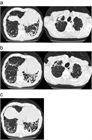

1. 上記のようなリスク因子を持つ患者に、亜急性から慢性の経過で、咳嗽、喀痰、発熱、呼吸困難、血痰・喀血などが出現したとき胸部画像検査にて、新たな空洞影の出現、空洞影の拡大、空洞壁の肥厚、空洞周囲浸潤影の拡大、fungus ball様の陰影などを認め、一般抗菌薬の投与に反応しない場合には、本症を疑う。